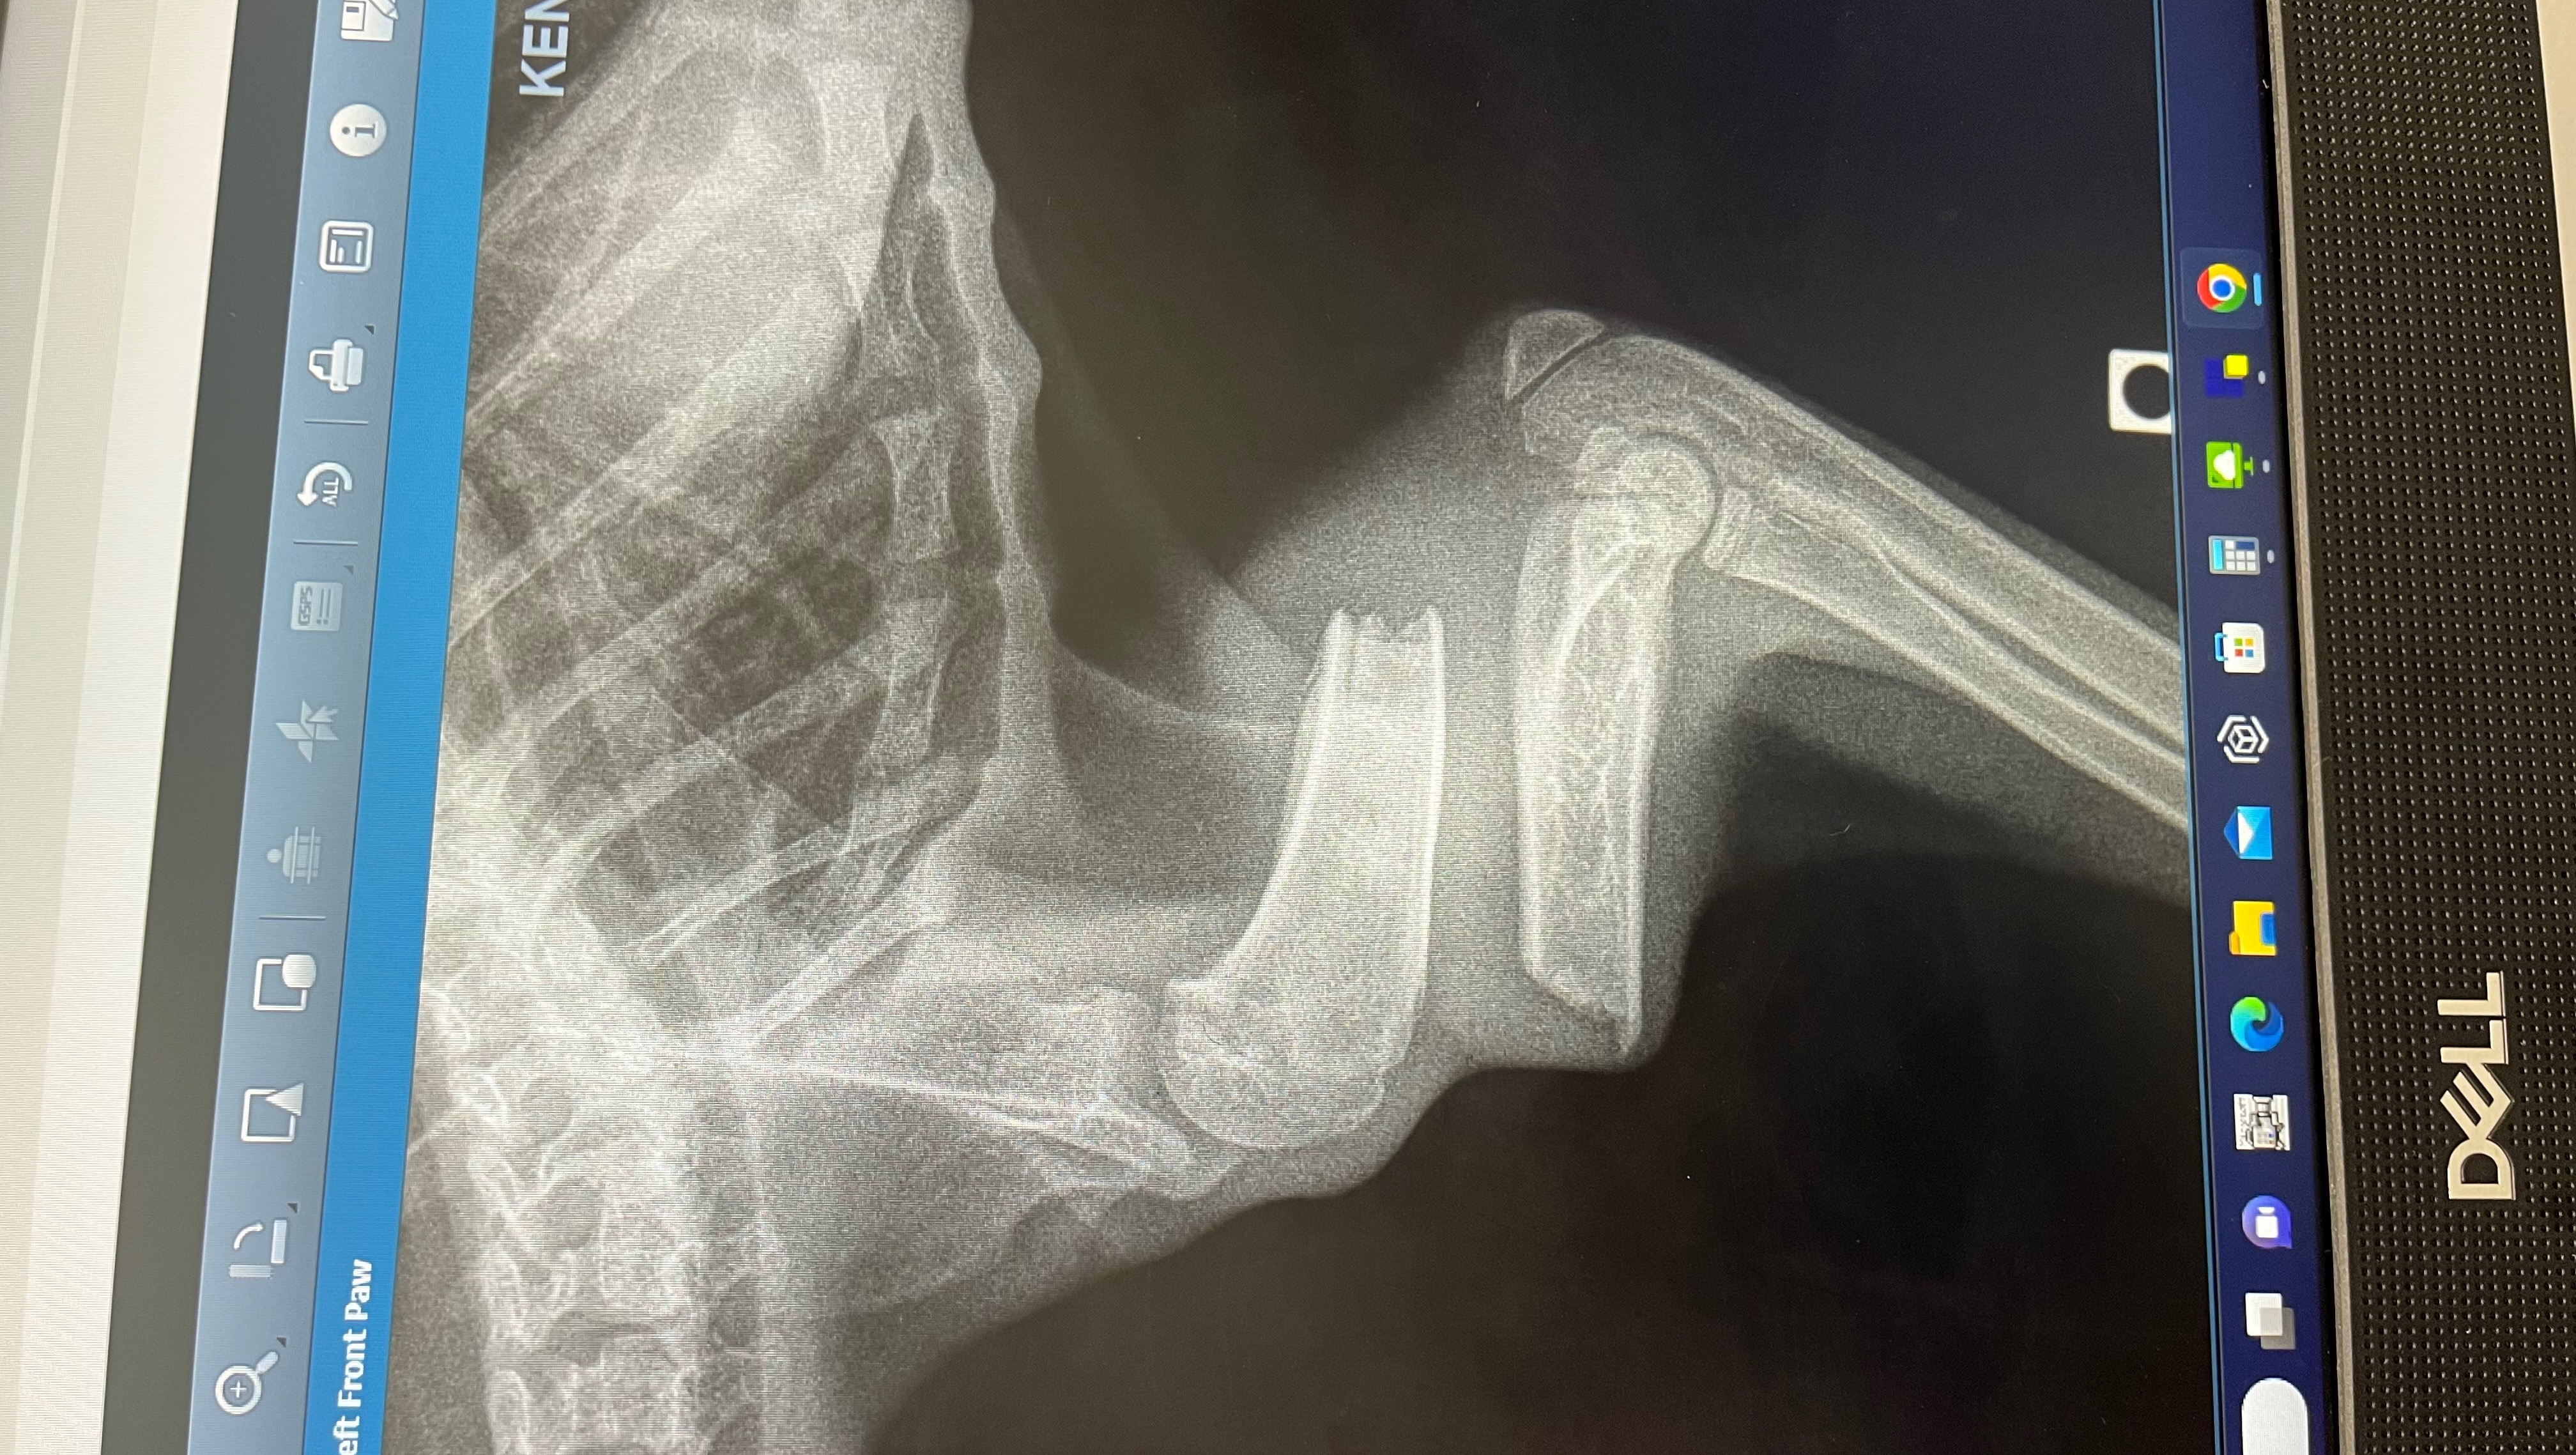

Hello, my name is Jocelyn I’m a foster for rescue cats/kittens in Miami. A few days ago I took in this 2 month old kitten, I named him Ollie. After seeing 3 vets it was determined that Ollie was hit by a car resulting in a broken front leg and abdominal hernia. Ollie is going to need 2 surgeries. Luckily I found a specialist that will perform both surgeries for $3,500. Ollie’s surgery is scheduled for Thursday August 24th. Ollie is a very strong and happy kitten who deserves a second chance. Please help me come up with the funds so Ollie can get his surgery, anything helps. Thank you so much. Below I have attached Ollie’s X-rays, vet bills so far & pictures of Ollie.